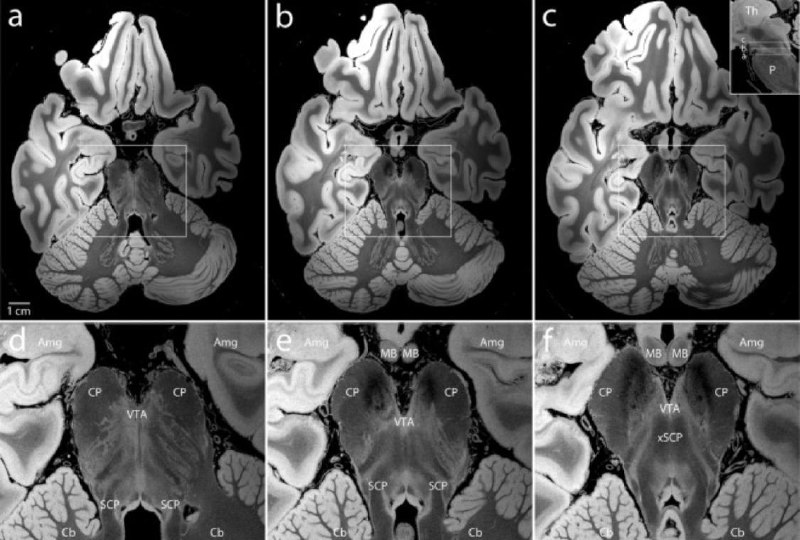

Магнитно-резонансная томография (МРТ) с высоким разрешением требует минимальной подготовки тканей, не вызывает искажений тканей и достигает 100 мкм на воксель в человеческом мозге ex vivo9. Однако этот тип МРТ требует 100 часов и не достигает разрешения, необходимого для видимости клеточных деталей.

Нейроанатомия ствола мозга. Репрезентативные поперечные срезы из синтезированного объема FLASH25 на уровне рострального моста и каудального среднего мозга. Увеличенные изображения ствола мозга, медиальной височной доли и переднего мозжечка (в белых прямоугольниках в a–c) показаны в нижнем ряду (d–f). Анатомические детали в этой МРТ с разрешением 100 мкм, далеко превосходят то, что можно увидеть на обычных МРТ in vivo: Amg = миндалина; Cb = мозжечки; CP = ножки мозга; MB = сосцевидное тело; P = pons; SCP = верхние мозжечковые ножки; VTA = вентральная покрышка; xSCP = перекрест верхних ножек мозжечка; Th = таламус.

10.1038/s41597-019-0254-8